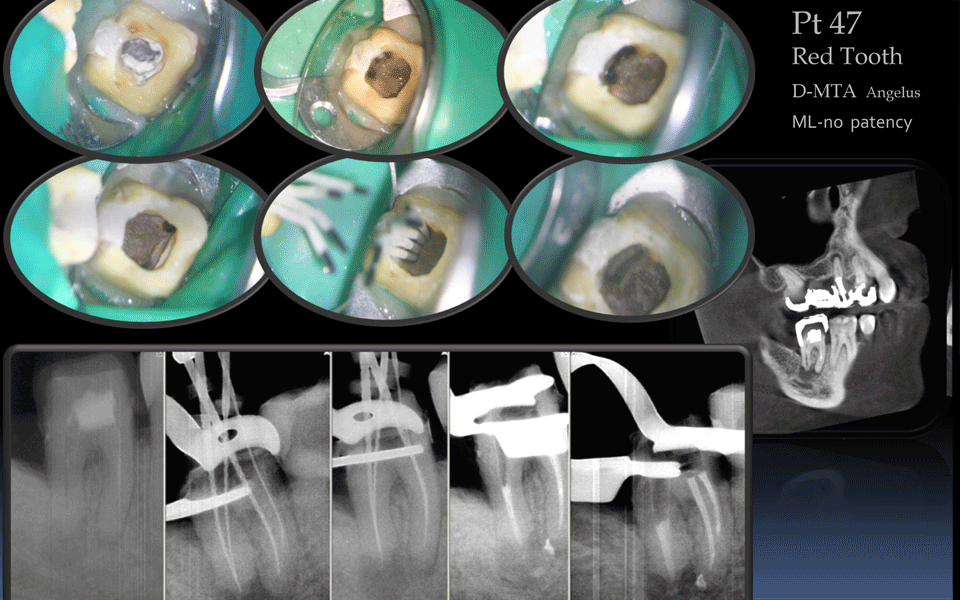

Перфорации

если случились перфорации (проколы) во время лечения зубного канала, нарушилась герметичность зуба, обнаружить и закрыть перфорации поможет микроскоп.